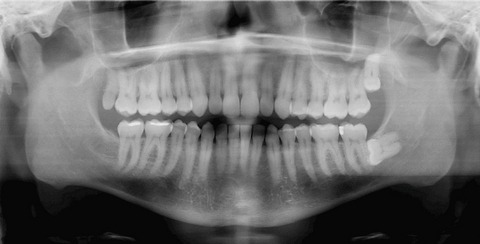

Alors pourquoi s’en prend t-on aux dents de sagesse ? Si elles existent c’est bien qu’elles doivent servir à quelque chose n’est-ce pas ? Effectivement mais bien des dentistes décident de les faire enlever à leurs patients pour anticiper un problème : infection lors de la pousse, déplacement des autres dents etc… Il arrive en effet que les dents de sagesse n’aient plus beaucoup de place pour pousser et qu’elles soient obligées de pousser les dents déjà en place. Ces troisièmes molaires sont donc enlevées de manière quasi systématique car ces opérations sont un business très lucratif !

Selon les spécialistes, retirer les dents de sagesse cause autant de problème que de les laisser… Selon un rapport publié dans l’American Journal of Public Health, plus de 67 % des extractions préventives de dents de sagesse étaient en fait parfaitement inutiles…mais quand on sait que cela représente 1 milliard de dollars de recette pour le secteur dentaire, on comprend vite pourquoi l’extraction préventive est systématisée….

En France, 1/3 des dents de sagesse sont retirées alors qu’elles auraient très bien pu rester dans votre bouche… de plus, les dents de sagesse ont une réelle utilité dans le sens où elles assurent le maintien de l’ensemble de la dentition. Il n’est pas rare que l’on voit suite à des extractions préventives arriver des problèmes de dents qui se déchaussent.